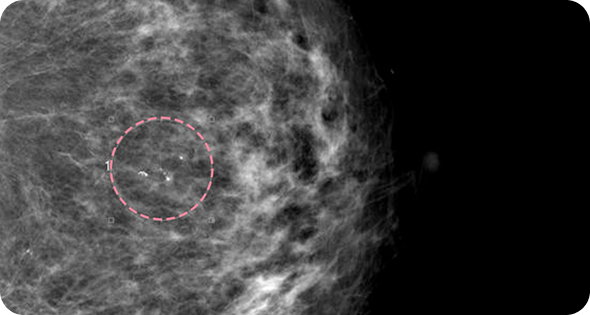

영상 특화 전문의니까

초음파 보면서

맘모톰도 안전하게

맘모톰시술 후 병리조직검사 결과 상피내암(조기 유방암) 초기로 진단되어 항암치료 없이 간단한 수술로 치료가 가능했습니다. 눈에 잘 띄지 않는 작은 병변까지 확인할 수 있었던 건, 맘모톰의 정밀한 조직검사 기능과 전문의의 정확한 판독이 있었기 때문입니다.